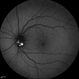

- gyrate atrophy, fundus autofluorescence (FAF)

- Imaging device

- Optos

- 50-year-old male came in with complaint of daytime vision loss for a year and nighttime vision loss for more than 20 years, gradually increasing day by day. Fundus showed paving-stone like areas of atrophy of the RPE involving the macula which coalesces to form a characteristic scalloped border at the junction of normal and abnormal RPE. Gyrate atrophy is an autosomal recessive dystrophy caused by tenfold elevations of plasma ornithine, which is toxic to the RPE and choroid. Patients with gyrate atrophy have hyperpigmented fundi, with lobular loss of the RPE and choroid, normally sparing the fovea. The finding of generalized hyperpigmentation of the remaining RPE helps to clinically distinguish gyrate atrophy from choroideremia. Affected patients usually develop night blindness during the first decade of life and experience progressive loss of visual field and visual acuity later in the disease course. Early diagnosis is crucial because treatment in form of Arginine free diet and oral pyridoxine helps in slowing the progression of disease.